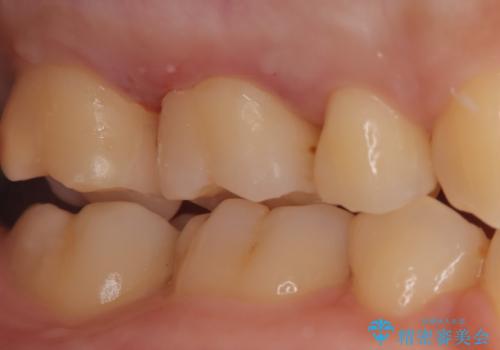

- 金属を外してセラミックを入れたいことを主訴に来院された患者さんです。

セラミックインレーにて修復を行いました。

当院でのセラミックインレーは、ラバーダムを使用して装着しております。